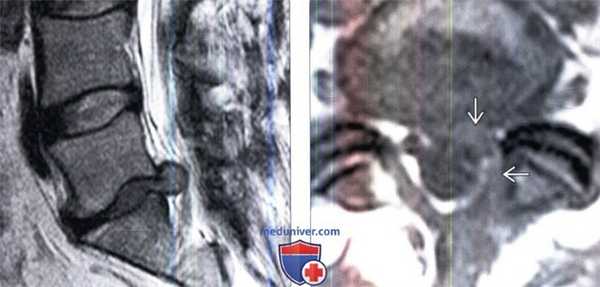

(Слева) Сагиттальный срез, Т2-ВИ: крупная рецидивная грыжа диска L5-S1. Видны признаки дегенерации этого диска в виде снижения его высоты и снижения интенсивности Т2-сигнала.

(Справа) На аксиальном Т1-ВИ определяются гомогенные изменения мягких тканей вдоль вентральной и левой боковой поверхности дурального мешка с минимальной деформацией последнего — это типичная картина перидурального фиброза.